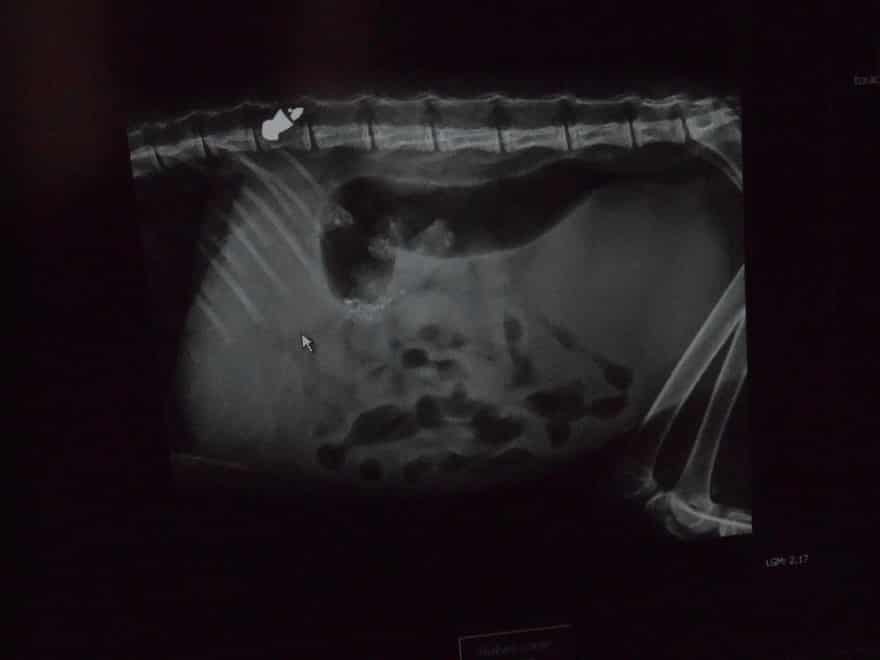

Tutti, data la qualità “cat friendly” della zona hanno pensato a un investimento, un caso sfortunato. E invece la visita dal veterinario ha evidenziato un’orribile verità : la presenza di un proiettile di piombo nella spina dorsale.

Il proiettile è stato consegnato ai Carabinieri, ed ora non si può che sperare in un’indagine. Alla vicenda si sono interessate anche le associazioni  Gruppo Ambiente di Ronchi dei Legionari e Gati de Monfalcon.